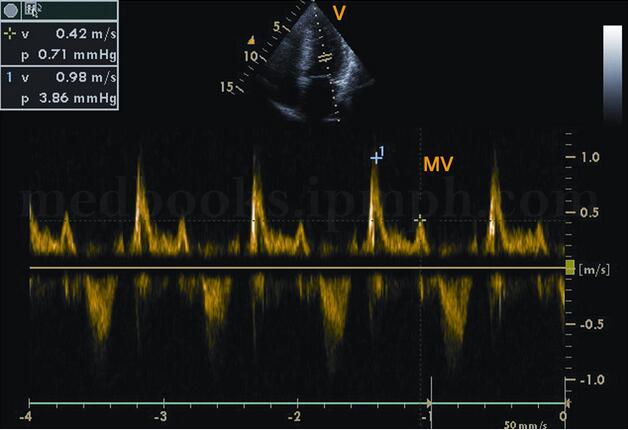

(2)二尖瓣口血流频谱异常的形态随疾病时期和程度不同,表现形式各异。①早期:A峰增高,E峰减低,E/A<1.0(图2‐1‐191)。②中期:呈“假性正常化”,二尖瓣E峰正常或稍增高,A峰减低,E/A>1.0(见图2‐1‐192)。DTI可以帮助鉴别这种“假性正常化”。③晚期:“限制性”充盈,E峰呈高耸的尖峰波,A峰极低或消失,E/A>1.5~2.0(图2‐1‐193)。

图2‐1‐192 二尖瓣口血流频谱:当舒张功能减低到一定程度出现E峰增高的假性正常化,E/A>1.0

图2‐1‐193 二尖瓣口血流频谱:舒张功能进一步减低,出现“限制性”充盈不良,E峰呈高耸的尖峰波,A峰极低或消失,E/A>2.0